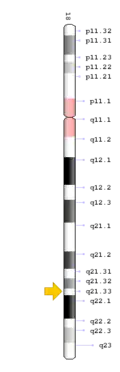

TCIRG1 mutation

The TCIRG1 gene is present in chromosome locus 11q13, which encodes for the a3 subunit of vacuolar H+ ATPase (V-ATPase) that is unique to osteoclasts.[12] The a3 subunit is responsible in anchoring the vacuolar proton pump to the ruffled membrane of osteoclasts.[9] The V-ATPase is important in mediating the transport of hydrogen ions into the resorption lacunae, which is a pit on the bone surface enclosed by the osteoclast for bone resorption. The accumulation of ions in the lacuna facilitates the decomposition of hydroxyapatite crystals by creating an acidic environment, resulting in bone resorption.[12]

Mutation of the gene results in osteoclast-rich osteopetrosis due to poor translation and altered structure of proton pump structure, which is normally involved in large amounts of osteoclast activity leading to absorption of bone tissue.[12] Mutation of TCIRG1 gene may arise from deletion or gene splicing defects, leading to frame-shifts of the nucleotides of the gene.[12]

TCIRG1 mutations illustrate the heterogeneity of DSS through a case study where DSS occurred due to a frameshift mutation, in conjunction with a mutation at an intron located in the gene in one of the alleles of chromosome 11 resulting in a splice site mutation.[9] Despite a frameshift mutation altering the C-terminal of the proton pump, due to increased remnant expression of the wild type transcript, it only resulted in intermediate autosomal recessive DSS due to the partial retainment of vacuolar proton pump function.[9]